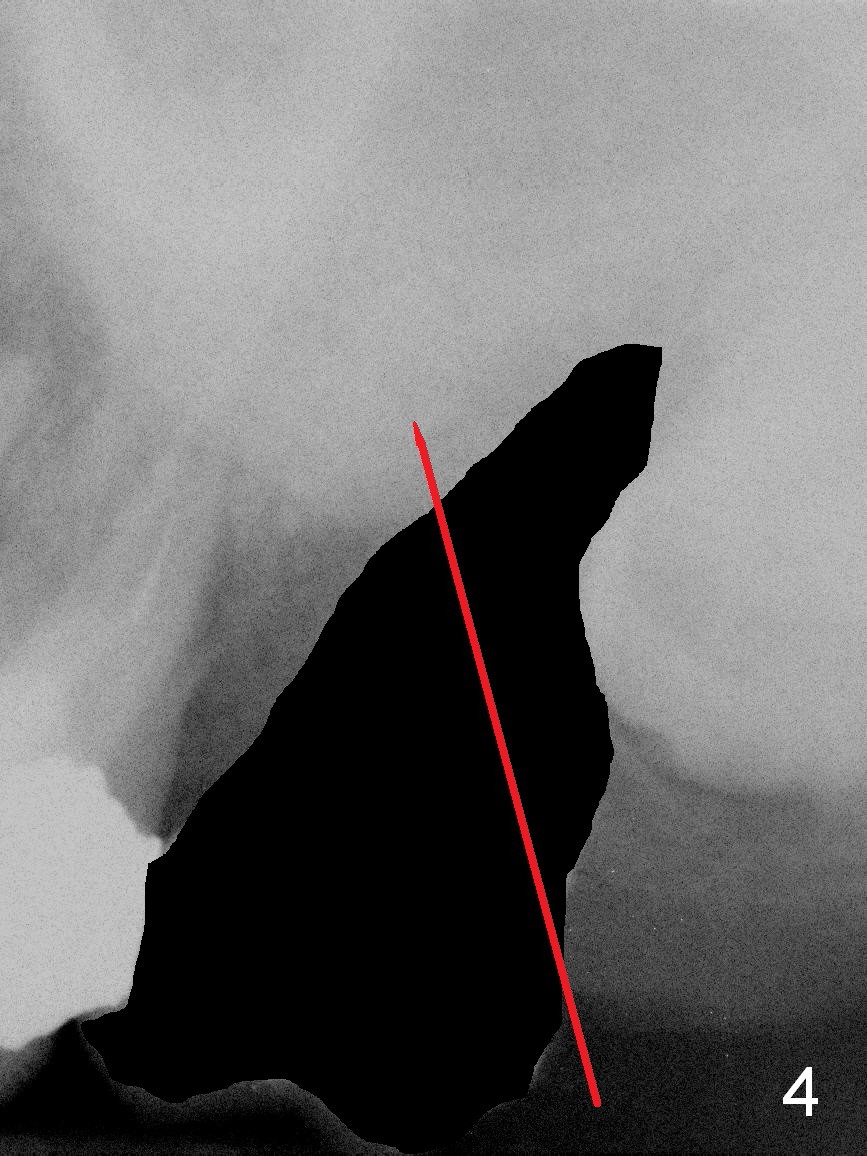

A 51-year-old lady (ZC) requests #15 extraction and immediate implant (Fig.1,2). The affected tooth is between periapical radiolucency of #14 (Fig.1 >) and the impacted 3rd molar (*). Discuss the possibility of extracting #14 and 16 at the same time. After extraction (Fig.3), osteotomy is initiated on the mesial slope of the socket (treated with Clindamycin, Fig.4). Once the cortex is penetrated, the trajectory is changed (Fig.5). After withdrawing the pilot drill, insert a parallel pin for X-ray. Adjust osteotomy position and angulation and finish placing an implant (Fig.6).